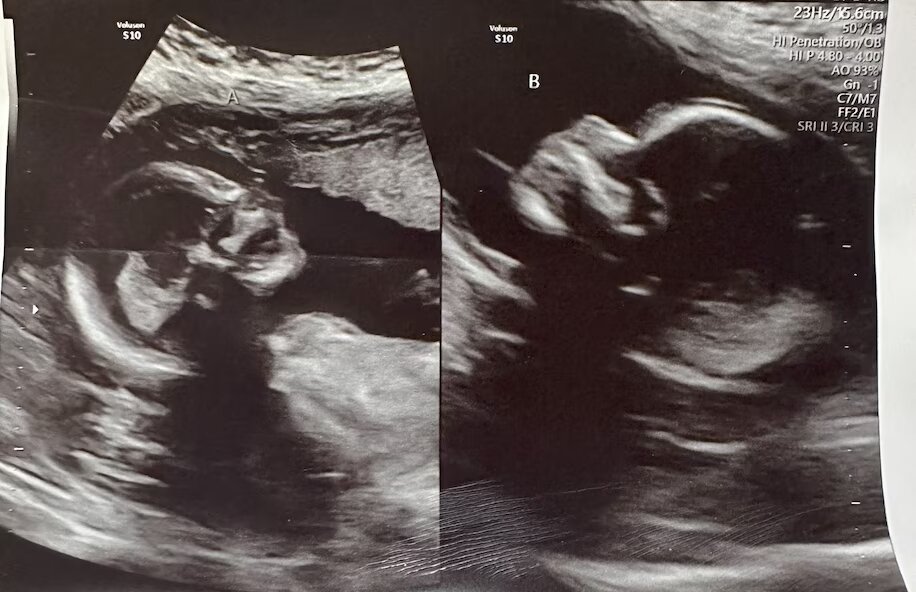

هاچر در ۸ هفتگی بارداریاش برای اولین سونوگرافی به بیمارستان رفت. هاچر وقتی پرستاری که سونوگرافی را انجام میداد، در ابتدا فقط یک جنین را در رحم راست او پیدا کرد، احساس راحتی کرد. اما هنگامی که پرستار رحم چپ را هم بررسی کرد، جنین دیگری در آن یافت.

هاچر گفت نمیتوانست این خبر را باور کند و شروع به خندیدن کرد. پرستار دکتر شوتات پاتل، متخصص زنان را صدا کرد و او چندین بار تصاویر را بررسی کرد تا مطمئن شود در هر یک از دو رحم هاچر جنین جداگانهای وجود دارد.

به گفته دکتر پات در بسیاری از زنانی که دو رحم دارند، فقط یک رحم کاملاً رشد کرده و دارای عملکرد است. او گفت احتمالا تخمکهای هاچر از طریق دو لوله فالوپ یا تخمدانی مجزای او به رحمهای جداگانهاش سفر کردهاند.